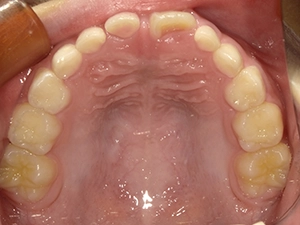

実際に小野歯科医院で行っているマイオブレースを用いた小児矯正の症例を紹介します。

どんどんきれいな歯並びになっていく様子を一緒に確認していきましょう!

2か月後

5か月後

6か月後

経過観察中…